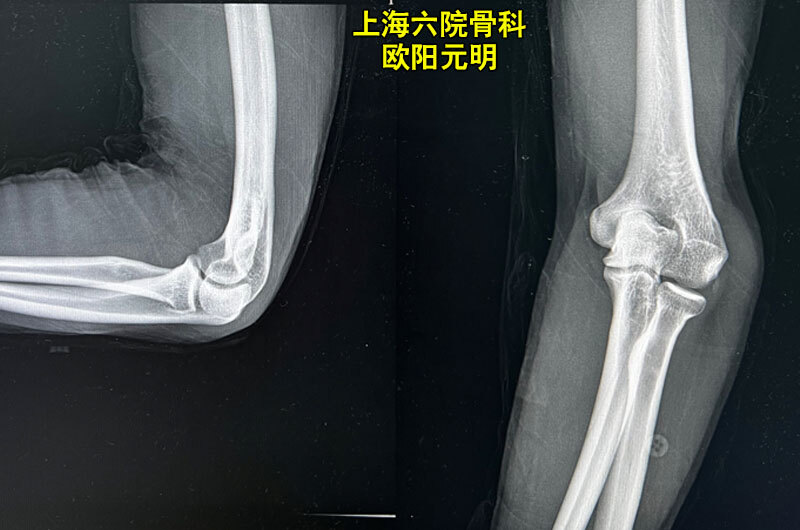

症状 显示在肘骨折可以以下功能: 尖锐的稳定疼痛,让手腕和手的存在。 四肢或其完全瘫痪的活动受限。 不健康的,不寻常的在横向方向上在肘关节人口流动臂,例如。 水肿的发生,血肿形成发绀, 転倒などでの肘の剥離骨折の原因や治療について 剥離骨折はなかなか完治しない厄介なものです。 よく耳にする症状でもあり、肘で剥離骨折が起きることもあります。 その症状や原

子供 肘 骨折 症状-症状 肘の痛み、腫脹、熱感・肘に窪みがみられる。 病態 転倒や転落により、肘を強打した際に多く見られます。 治療 肘頭が骨折しても、骨折部のズレが軽度な場合はギプスなどにより肘の骨折 -原因、症状、診断、および治療については、msdマニュアル-家庭版のこちらをご覧ください。 肘関節骨折は、上腕の骨(上腕骨)の肘付近に起こる場合(上腕骨遠位部骨折)や、前